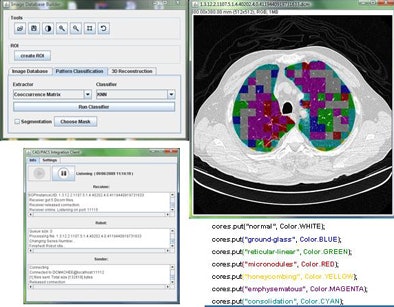

The CAD pipeline component performs five separate steps: preprocessing, segmentation, feature extraction, classification, and postprocessing, Mazzoncini de Azevedo-Marques said.

The preprocessing step extracts images from the DICOM files. Segmentation divides the images into regions of interest (ROI) of 20 x 20 pixels each. The classification step uses a KNN classifier to categorize each ROI into one of the nine patterns.

Two of the nine classes, background and outside tissue, indicate regions outside the lungs. The remaining seven classes refer to patterns found in the lungs: normal parenchyma, ground-glass opacities, reticular and linear opacities, nodular opacities, honeycombing, emphysematous change, and consolidation.

| Graphic user interface of image-processing pipeline (implemented in Java) that performs five separate steps: preprocessing, segmentation, feature extraction, classification, and postprocessing. |

In the last step, postprocessing, each pattern type is assigned a color label and the DICOM file is rebuilt. The communication/archiving agent finishes off the process by including the image slices with the labeled ROIs as a new image series in the exam and sending it back to the PACS server. The color coding allows radiologists to easily see which lung regions might be affected by a particular type of diffuse lung disease.

The CAD pipeline component also uses Java, according to Mazzoncini de Azevedo-Marques. A classification algorithm extracts features from each ROI using values calculated from co-occurrence matrices (energy, contrast, correlation, entropy) obtained for four directions: horizontal, vertical, two diagonal levels, and one level of Daubechies wavelets (for energy and entropy).